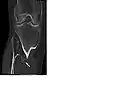

The diagnosis of HMO is based upon establishing an accurate correlation between the above-mentioned clinical features and the characteristic radiographic features. Family history can provide an important clue to the diagnosis. This is supplemented by testing for the two genes in which pathogenic variants are known to cause HMO namely EXT1 and EXT2. A combination of sequence analysis and deletion analysis of the entire coding regions of both EXT1 and EXT2 detects pathogenic variants in 70–95% of affected individuals.[3][4] The hallmark of radiographic diagnosis is the presence of osteochondromas at the metaphyseal ends of long bones in which the cortex and medulla of the osteochondroma represent a continuous extension of the host bone. This is readily demonstrable in radiographs of the knees.[3][1]

CT of osteochondroma in MO